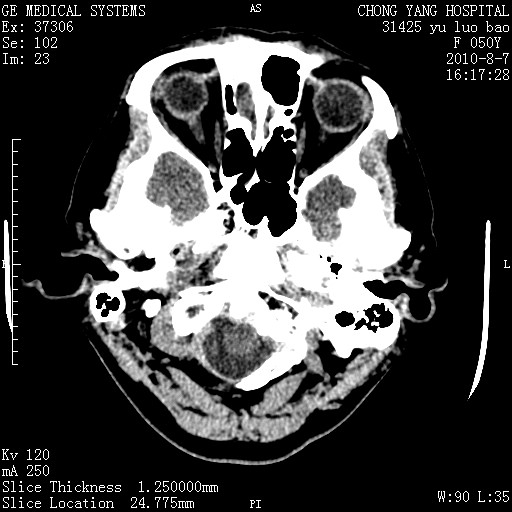

标题: CT28285:听力下降一年,头昏。 [打印本页]

标题: CT28285:听力下降一年,头昏。

右侧桥小脑角区占位--听神经瘤,建议增强或mri检查。

右侧桥小脑角去等密度占位,右侧内听道扩大、骨质吸收,考虑:右侧听神经瘤,建议增强检查。

右侧内听道扩大、骨质吸收,中脑受压左移,考虑:右侧听神经瘤,建议增强检查。支持!

右侧桥小脑角区等密度占位,内耳道扩大,听神经瘤